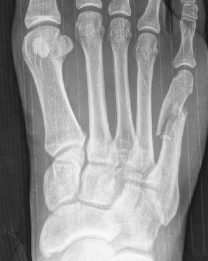

Xray

Zone 2 fractures

Union of zone 2 fracture with nonoperative care

Progression to nonunion of zone 2 fracture with nonoperative care